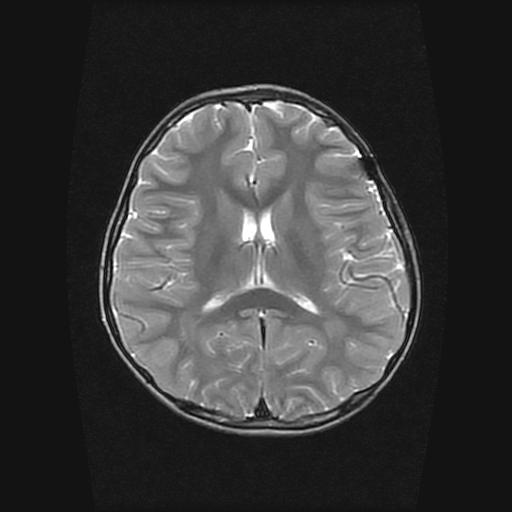

标题: PED0377: 6岁小儿,左侧视神经瘤术后 [打印本页]

标题: PED0377: 6岁小儿,左侧视神经瘤术后

6岁小儿,左侧视神经瘤术后。现左侧视力减退。